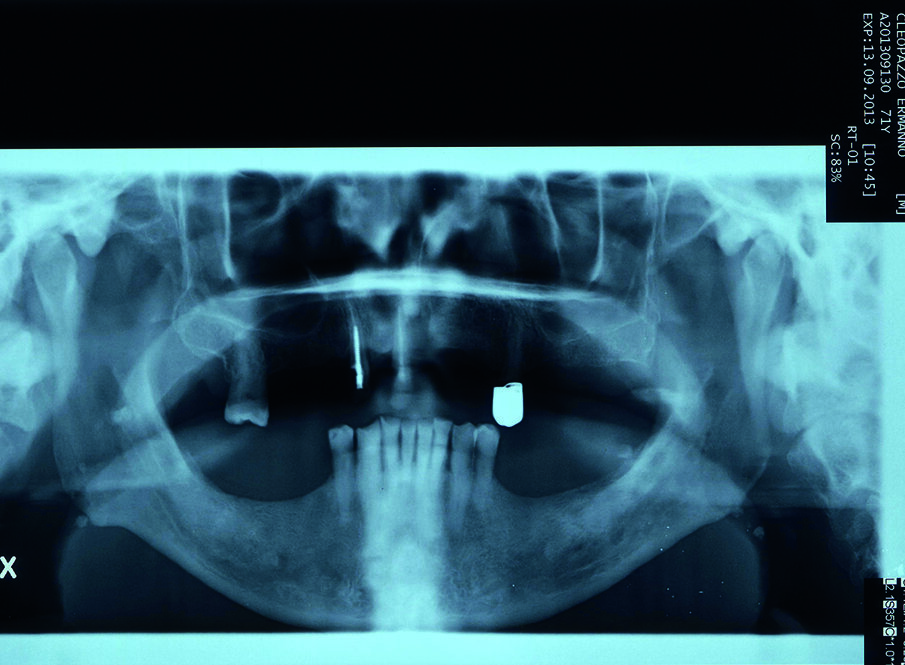

Si presenta alla nostra osservazione un paziente di anni 75, pensionato, con una richiesta di riabilitazione orale. Il paziente presenta edentulia parziale con distruzione dei tavolati occlusali e diminuzione della dimensione verticale (Fig. 1). In sede mandibolare sono conservati gli elementi dentali dal 35 al 45, mentre a livello mascellare residuano 4 elementi dentali con gravi problemi endodontici, di carie e parodontali. All’anamnesi si evidenzia la presenza di un diabete di tipo 2. Nessun problema è stato rilevato a livello ematico e pressorio.

Condividiamo con il paziente la scelta terapeutica di riabilitazione implantoprotesica che nella 1 fase consisterà in riabilitazione occlusale mediante l’applicazione di protesi provvisoria, e successivamente inserimento di 6 impianti nel mascellare a carico ritardato e seguente applicazione di barra per una overdenture. Il paziente necessita di una riabilitazione oro-implantare protesica, in quanto sia all’esame obiettivo che all’esame radiografico presenta una ridotta dimensione verticale che negli anni ha portato alla distruzione degli elementi inferiori dal 34 al 44, e persistenza di 11, 13, 17, 25 che presentano abrasioni e abfrazioni sulla superficie coronale (Fig. 2). Dopo aver condiviso con il paziente le problematiche terapeutiche dovute anche alla sua condizione di patologia sistemica, si decise, di procedere con avulsione dei denti dell’arcata superiore e contestuale inserzione di 6 impianti, per un una riabilitazione implantoprotesica overdenture su barra, a carico ritardato a 6 mesi.

La tecnica chirurgica scelta permetterà di ridurre la durata dell’intervento e il rischio operatorio: sanguinamento, calo di glicemia, rischio di infezioni. È stato utilizzato un anestetico con una bassa concentrazione di adrenalina al fine di evitare un effetto iperglicemizzante ed è stata eseguita una terapia preventiva della sepsi per evitare qualsiasi rischio al paziente diabetico (Figg. 3a, 3b).